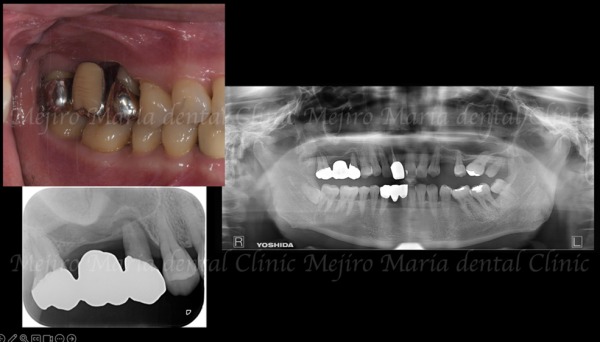

治療後の様子

サイナスリフト後6ヶ月(抜歯から10ヶ月)で、インプラントを理想的な位置に安全に埋入できました。術後の上顎洞や歯肉にも炎症は認められません。

右上で噛む力を支えられるようになったことで前歯の負担が軽減し、同時に行っていた矯正治療により左側の噛み合わせも改善したことで、長期的に安定した咬合が期待できます。

※現在、左側の咬合の回復のための治療を継続しています(2025年12月現在)